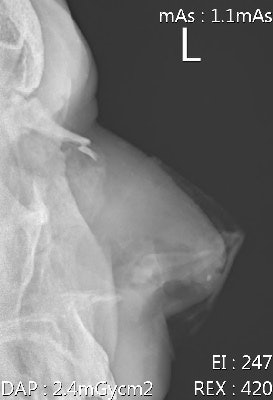

Hamstring strains and injuries are common in fast bowlers. Injuries of the hands/fingers such as avulsion fractures and dislocations are usually a result from a player catching the ball and are common. Rotator cuff injuries are often seen in fast bowlers and fielders, with labrum injuries commonly seen in fielders.

Additional forces are transmitted to the spine through the lower limb, while additional forces at the lumbo-sacral junction are caused by trunk hyperextension, lateral flexion, and twisting during the delivery stride. Outfield players (fielders) and bowlers do not wear any protective equipment, except close-in fielders, who wear helmets. The wicket keeper usually wears a helmet, gloves, and pads. The batsman is the best protected of them with helmet, gloves, and leg and forearm pads.